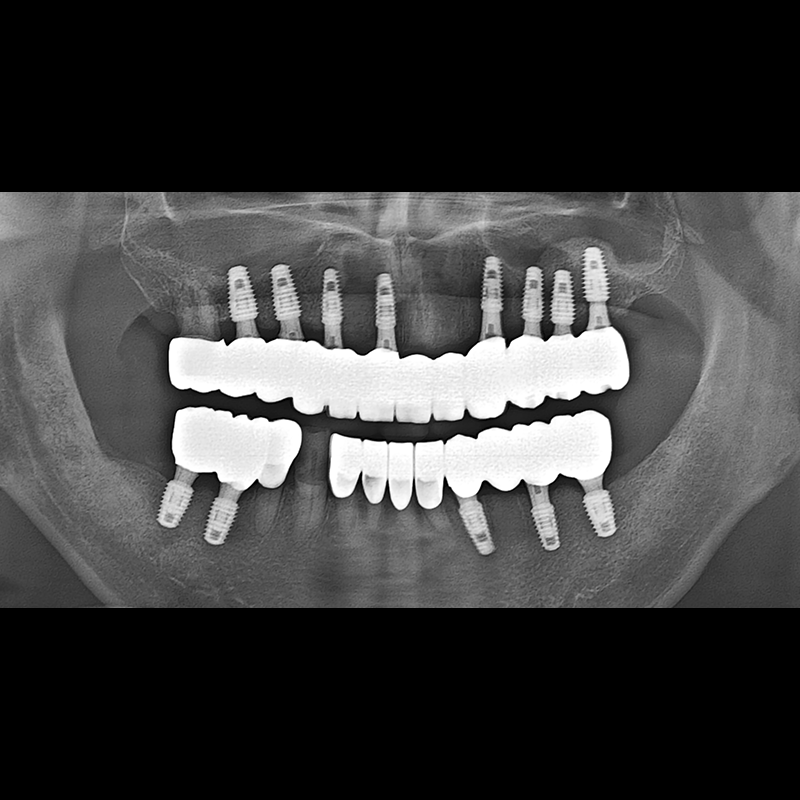

BEFORE AFTER

种植牙前后的照片 2025.05.30

在缺失的牙齿部分和难以挽救的牙齿位置植入了种植牙。